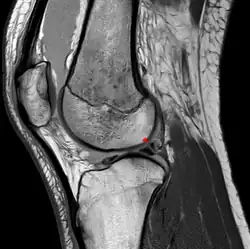

Posterior meniscofemoral ligament on MRI, sagittal -